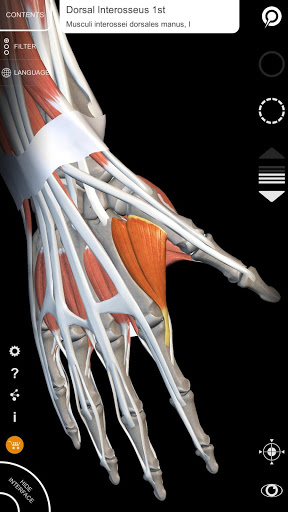

"Anatomy 3D Atlas" memungkinkan Anda mempelajari anatomi manusia dengan cara yang mudah dan interaktif.

Melalui antarmuka yang sederhana dan intuitif, Anda dapat mengamati setiap struktur anatomi dari sudut mana pun.

Model 3D anatomi sangat terperinci dan memiliki tekstur hingga resolusi 4k.

MODEL ANATOMI 3D

• Sistem muskuloskeletal